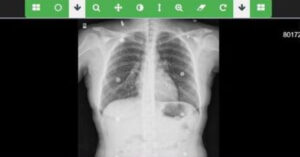

Doğuştan kalp hastalığı bulunan, ileri derecede kalp yetmezliği yaşayan 11 yaşındaki çocuk, kalbinin durduğu kritik anda uygulanan açık kalp cerrahisi sayesinde yeniden hayata döndürülerek sağlığına kavuştu Gaziantep’te yaşayan doğuştan aort kapak hastası Azat Enes Aslan, iki ay önce acil olarak Sağlık Bakanlığına ait uçak ambulansla İstanbul’daki Koşuyolu Yüksek İhtisas Eğitim...